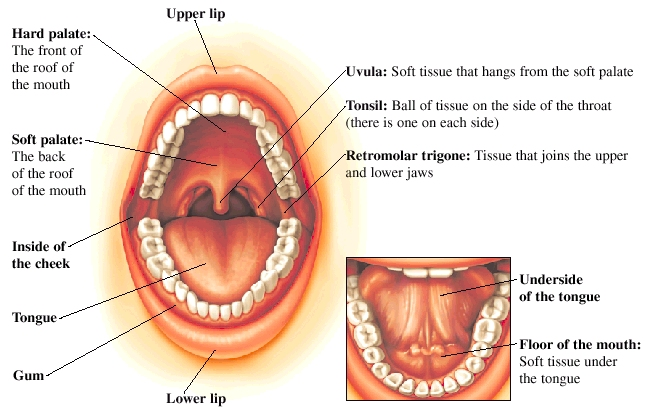

Oral Cancer Mouth Cancer Anatomy Headandneckcancerguide Org

Early Stage Oral Cavity Cancer Memorial Sloan Kettering

Mouth Cancer Memorial Sloan Kettering Cancer Center

Stages Of Oral Cancer Mouth Cancer Headandneckcancerguide Org